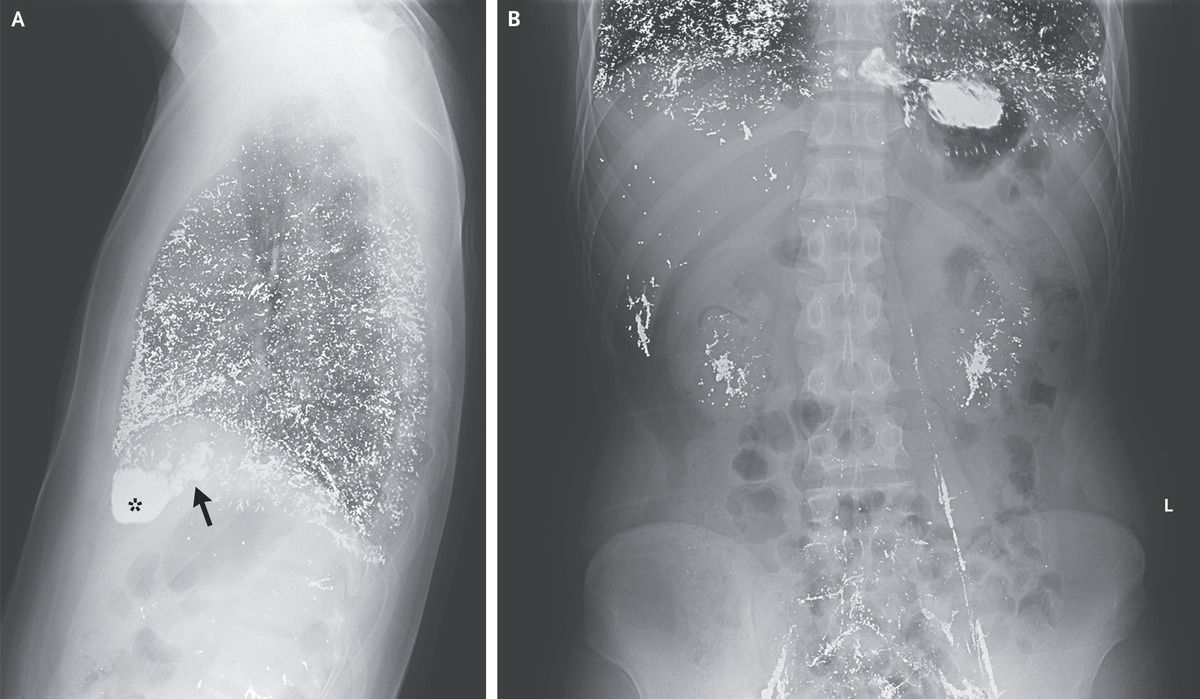

A previously healthy 25-year-old man presented to the general medicine clinic with a 3-month history of worsening fatigue, nausea, and dry cough. One week before the onset of his symptoms, he had injected 4 ml of elemental mercury intravenously as a folk remedy for tinea cruris. Conjunctival pallor was observed on physical examination. Laboratory studies showed a hemoglobin level of 6.5 g per deciliter (reference range, 12.0 to 16.0), a serum mercury level of 430 μg per deciliter (21,440 nmol per liter; reference value, <1.5 μg per deciliter [70 nmol per liter]), a 24-hour urine mercury level of 29,792 μg (148,510 nmol; reference value, <45 μg [220 nmol]), and normal renal function. A chest radiograph (Panel A) showed diffusely distributed metallic opacities in the lungs, right atrium (arrow), and right ventricle (asterisk). An abdominal radiograph (Panel B) showed similar metallic densities in the liver, kidneys, iliac veins, and left gonadal vein. A diagnosis of mercury poisoning was made. Inpatient chelation therapy with intravenous unithiol was initiated. After 2 weeks of treatment, the patient’s symptoms had abated, his hemoglobin level had increased to 8.0 g per deciliter, and his serum mercury level had decreased to 254 μg per deciliter (12,660 nmol per liter). The patient was discharged from the hospital with a recommendation to continue chelation therapy with oral dimercaptosuccinic acid.